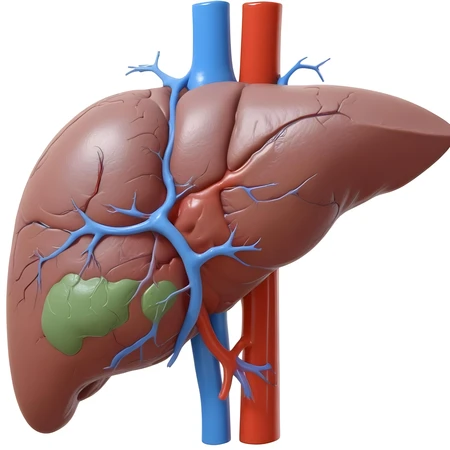

digital painting liver

34 Photos